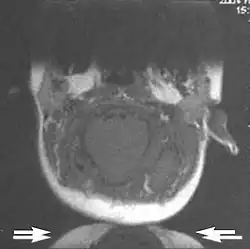

Metal artifacts

Metal artifacts occur at interfaces of tissues with different magnetic susceptibilities, which cause local magnetic fields to distort the external magnetic field. This distortion changes the precession frequency in the tissue leading to spatial mismapping of information. The degree of distortion depends on the type of metal (stainless steel having a greater distorting effect than titanium alloy), the type of interface (most striking effect at soft tissue-metal interfaces), pulse sequence and imaging parameters. Metal artifacts are caused by external ferromagnetics such as cobalt containing make-up, internal ferromagnetics such as surgical clips, spinal hardware and other orthopaedic devices, and in some cases, metallic objects swallowed by people with pica.[3] Manifestation of these artifacts is variable, including total signal loss, peripheral high signal and image distortion (Figs 3 and 4).[1] Reduction of these artifacts can be attempted by orientating the long axis of an implant or device parallel to the long axis of the external magnetic field, possible with mobile extremity imaging and an open magnet. Further methods used are choosing the appropriate frequency encoding direction, since metal artifacts are most pronounced in this direction, using smaller voxel sizes, fast imaging sequences, increased readout bandwidth and avoiding gradient-echo imaging when metal is present. A technique called MARS (metal artifact reduction sequence) applies an additional gradient, along the slice select gradient at the time the frequency encoding gradient is applied.